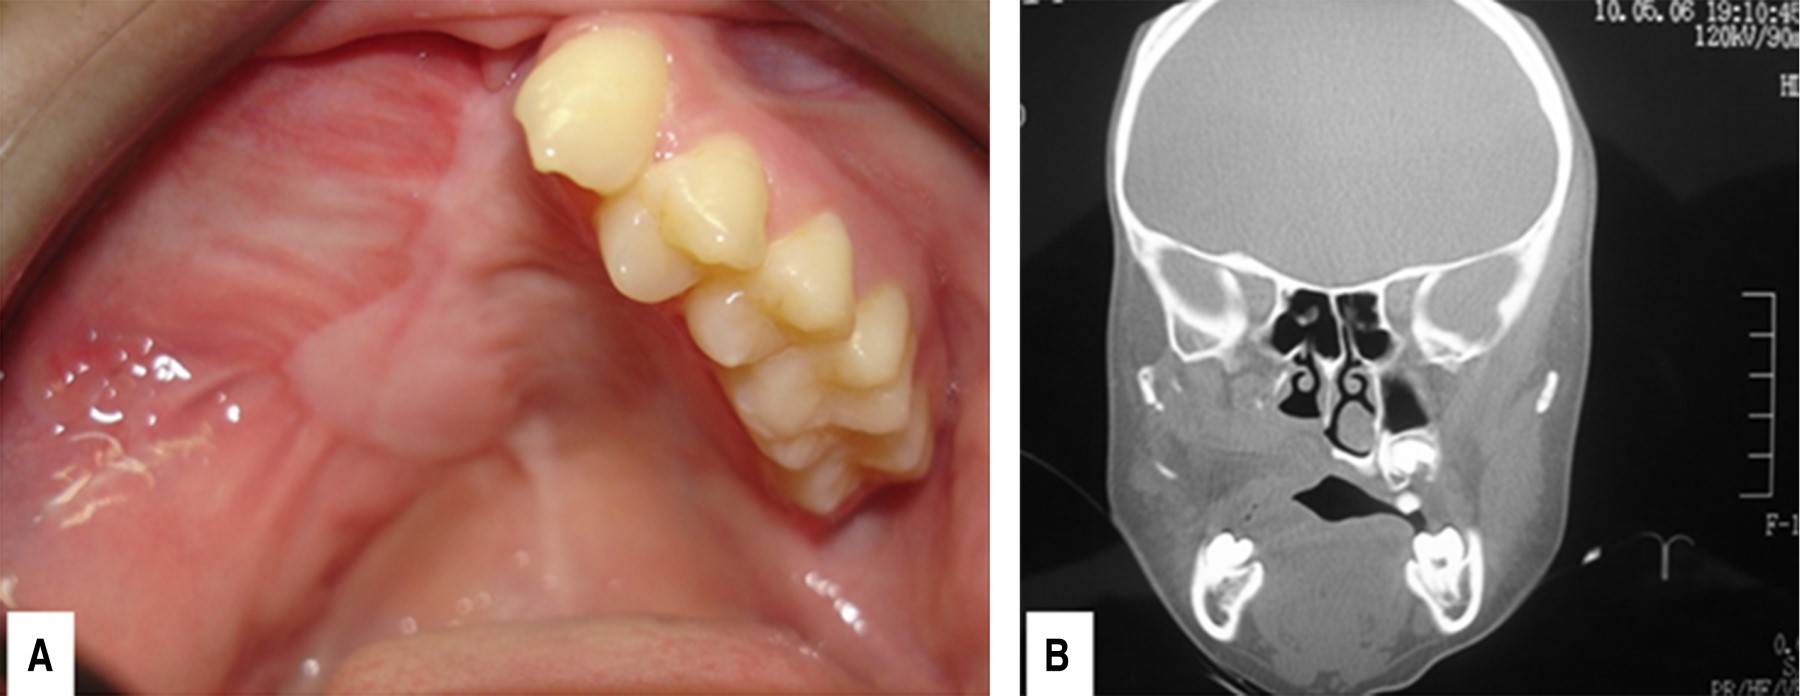

Figure 2